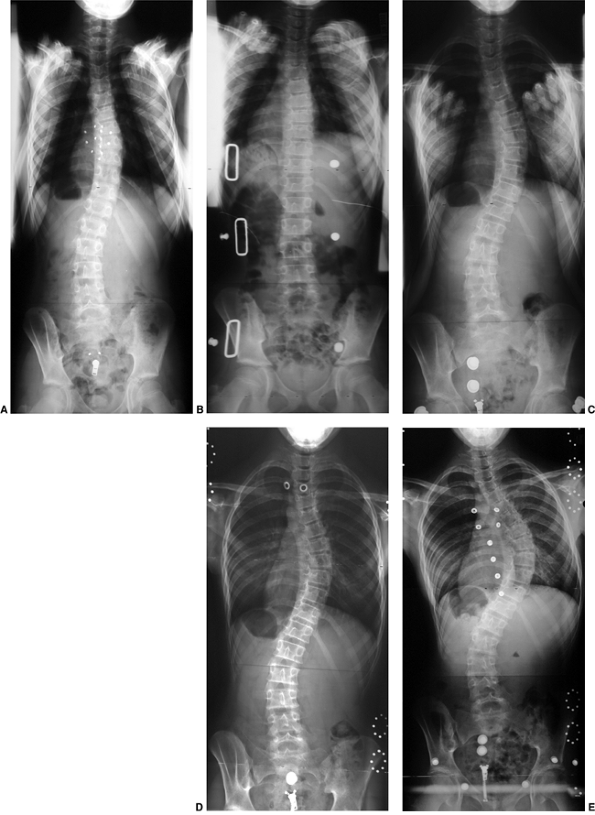

![]()  |

Figure 18.17 A:

This 4-month-old baby boy presented with a left thoracic scoliosis. A magnetic residence imaging (MRI) study was performed and found to be normal. He was therefore diagnosed with infantile idiopathic scoliosis. The rib vertebral angle difference was greater than 20 degrees, suggesting likely progression. B: At 3 years 2 months of age, after substantial progression and multiple attempts at casting, his curve has continued to increase with substantial chest wall deformity. C: At 9 years 2 months his curve has progressed to a severe degree. This was despite attempts at bracing, as well as subcutaneous growth rodding. His growth rods required removal after several years because of infection. This demonstrates the challenges of treating progressive infantile idiopathic scoliosis.  |